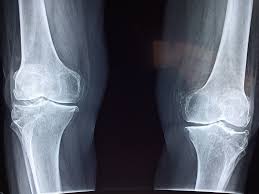

Votre capital osseux menacé en silence

Un effet peu connu des sodas, surtout des colas, touche à leur impact sur la solidité de notre squelette. Le problème ne vient pas d’un ingrédient en particulier, mais du fait qu’ils prennent souvent la place de boissons riches en calcium indispensables, telles que le **lait ou les laits végétaux enrichis**. Pour les ados et jeunes adultes, ce remplacement peut nuire à la construction d’une **ossature robuste**. Chez les personnes plus âgées, il peut accélérer une **dégradation lente** de la densité osseuse au fil des années.